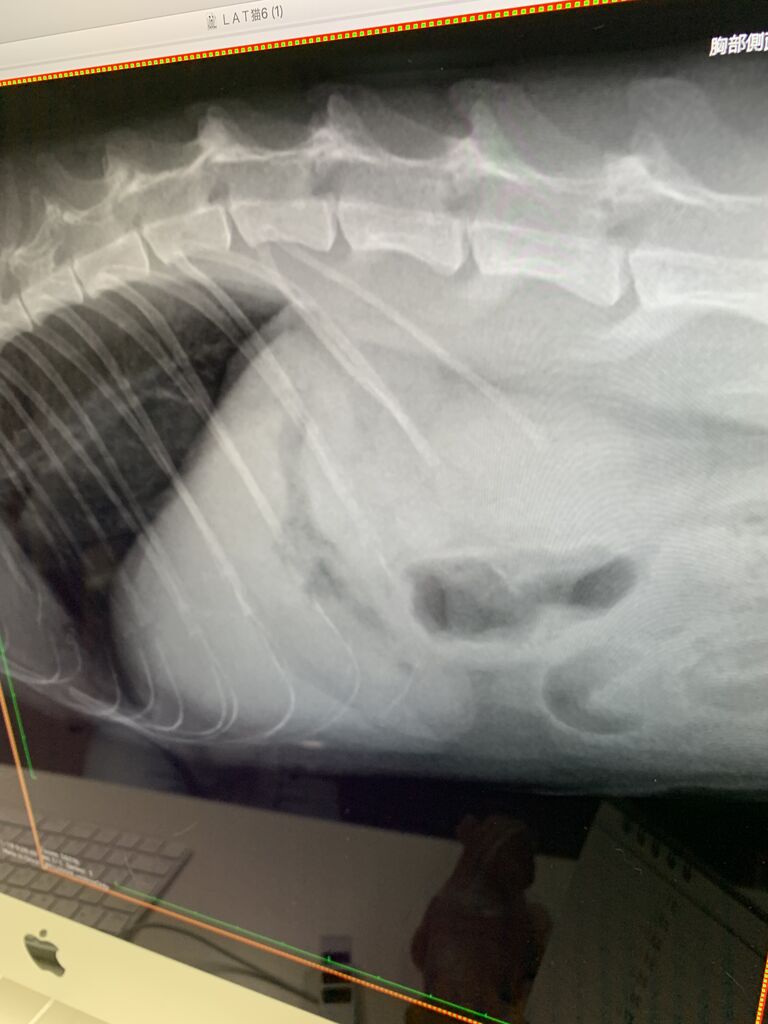

でも、微熱と言うか、40度ぐらいの熱が続くカカオは、若干、腹水もみられ、

最悪な事にFIPの診断が下されてしまいました。。。